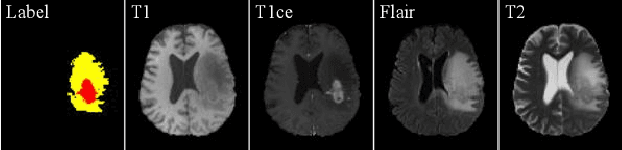

Due to the difficulties of obtaining multimodal paired images in clinical practice, recent studies propose to train brain tumor segmentation models with unpaired images and capture complementary information through modality translation. However, these models cannot fully exploit the complementary information from different modalities. In this work, we thus present a novel two-step (intra-modality and inter-modality) curriculum disentanglement learning framework to effectively utilize privileged semi-paired images, i.e. limited paired images that are only available in training, for brain tumor segmentation. Specifically, in the first step, we propose to conduct reconstruction and segmentation with augmented intra-modality style-consistent images. In the second step, the model jointly performs reconstruction, unsupervised/supervised translation, and segmentation for both unpaired and paired inter-modality images. A content consistency loss and a supervised translation loss are proposed to leverage complementary information from different modalities in this step. Through these two steps, our method effectively extracts modality-specific style codes describing the attenuation of tissue features and image contrast, and modality-invariant content codes containing anatomical and functional information from the input images. Experiments on three brain tumor segmentation tasks show that our model outperforms competing segmentation models based on unpaired images.